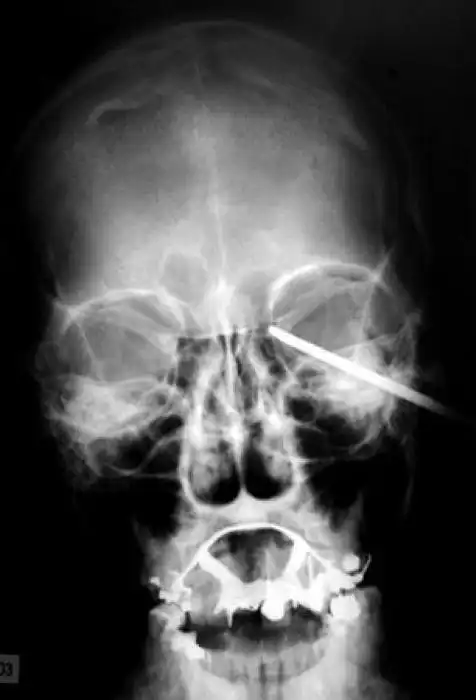

Необычные предметы в теле людей на рентгеновских снимках

На рентгеновских снимках людей порой можно обнаружить самые необычные предметы, которые находятся в их теле.

Человечество явно с гвоздями не дружит!!! Что не снимок то гвоздь в башке!